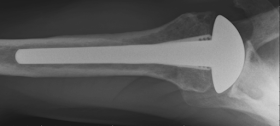

He has returned to full action on the the handball court. His 9 year post operative films are shown here, showing a well-fixed thin impaction grafted smooth stem